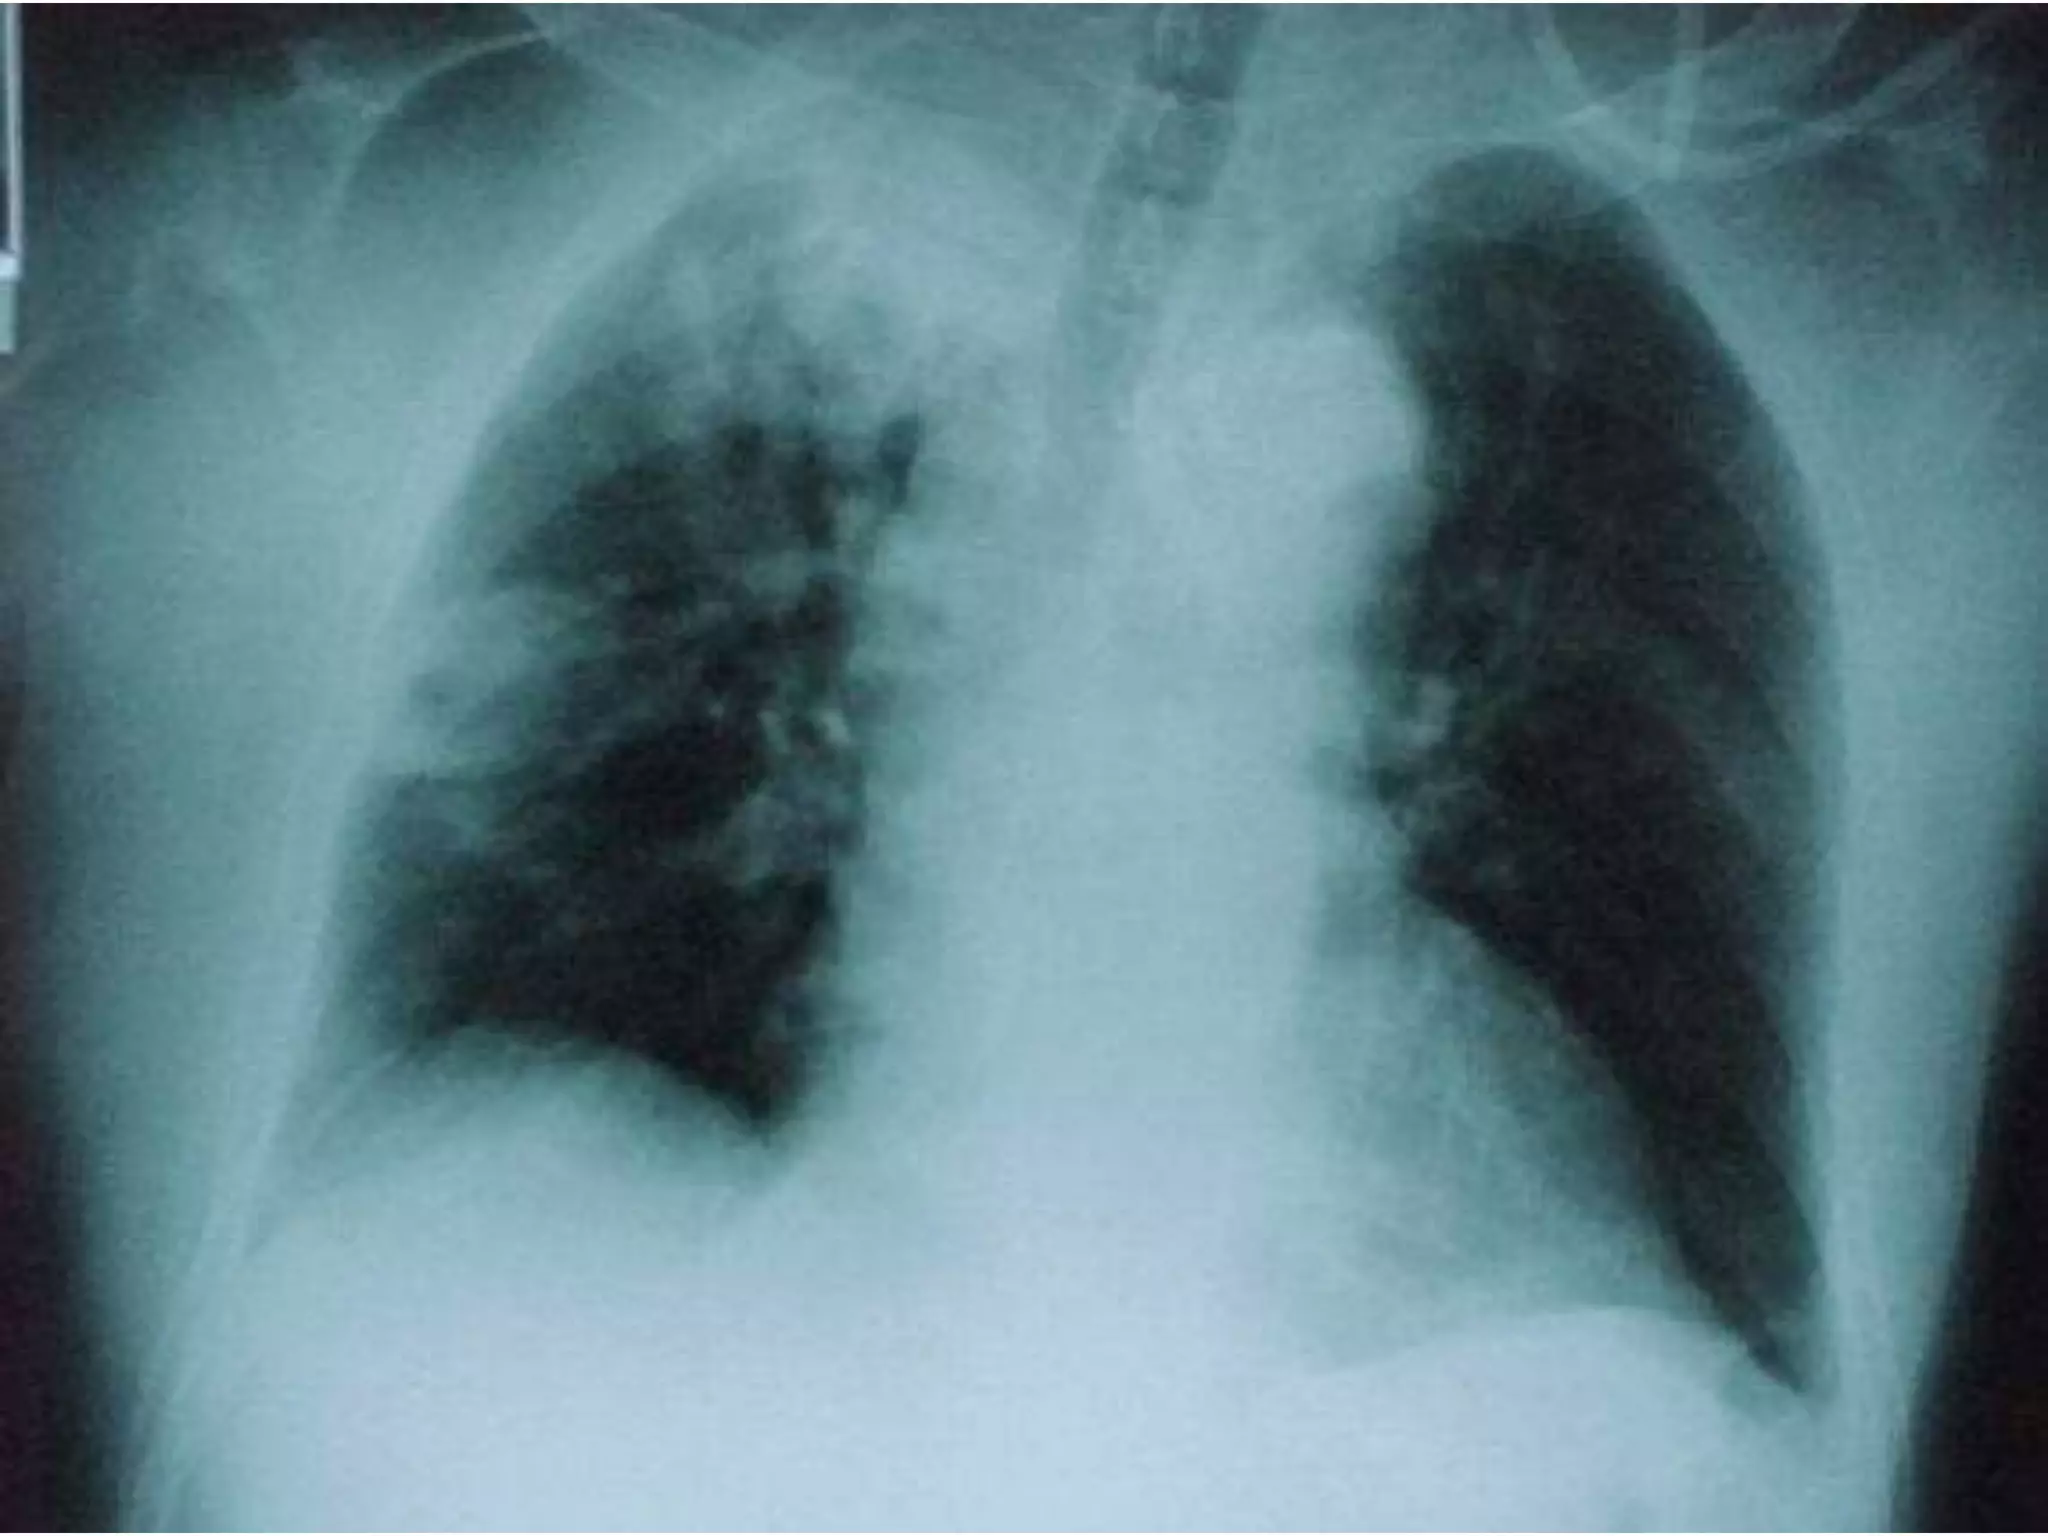

 Pulmonary disease: 70-75% isolates of

NTM

 Definition

 Usually adults

 Symptoms of cough, sputum production,

weight loss

 Two or more sputum isolates or one isolate

from, BAL, Bx, sterile site

 Distribution of isolates varies regionally

 MAC, rapid growers, M kansassi & M xenopi

 M.Kansasii

 Similar to TB

 US midwest and

south

 AFB positive

 Probe positive

 HIV CD4 <200

pulmonary and

disseminated

 M..xenopi

 UK, Northern

Europe and

Canada, less

common in US

 Rural /farm area

 Very good outcome

 X-RAY: chest, CAT thorax

 Pulmonary disease:70-75% isolates of NTM  Definition  Usually adults  Symptoms of cough, sputum production, weight loss  Two or more sputum isolates or one isolate from, BAL, Bx, sterile site  Distribution of isolates varies regionally  MAC, rapid growers, M kansassi & M xenopi

• 16.

 M.Kansasii  Similarto TB  US midwest and south  AFB positive  Probe positive  HIV CD4 <200 pulmonary and disseminated  M..xenopi  UK, Northern Europe and Canada, less common in US  Rural /farm area  Very good outcome